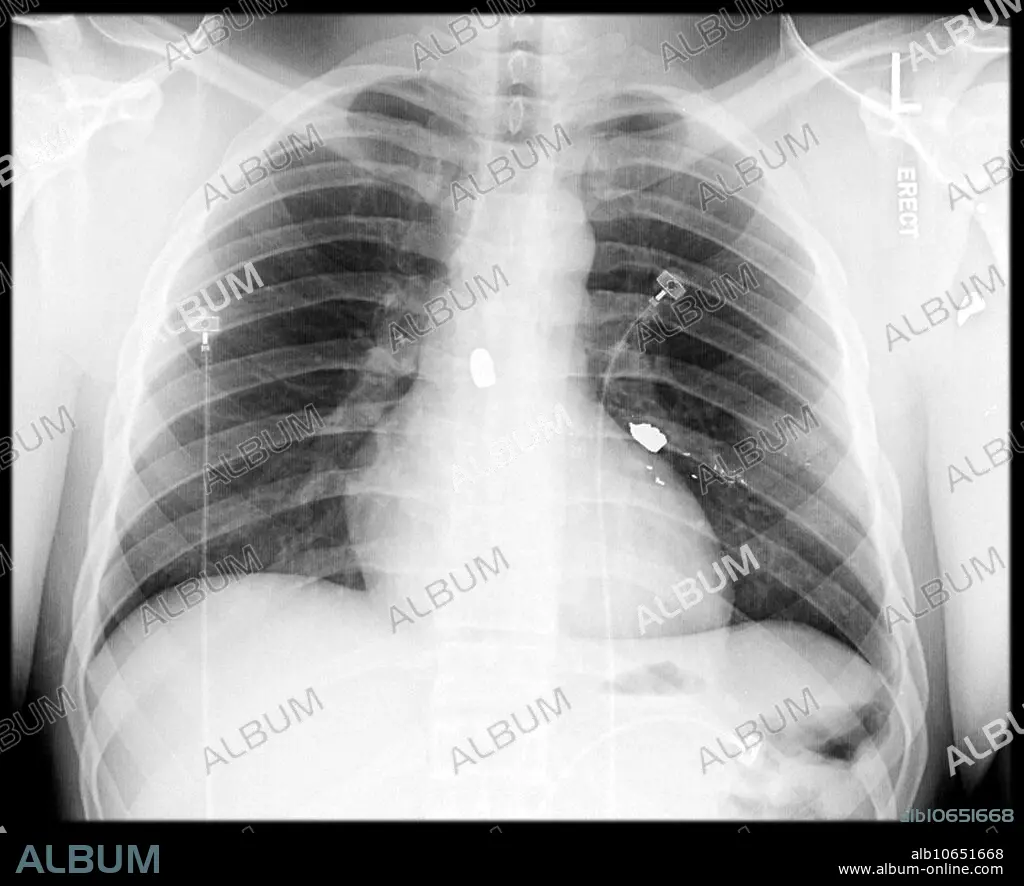

Multiple Bullet Fragments

This frontal chest x-ray shows multiple bullet fragments lodged in the soft tissue of the chest. These show up as very white because of the metal content.